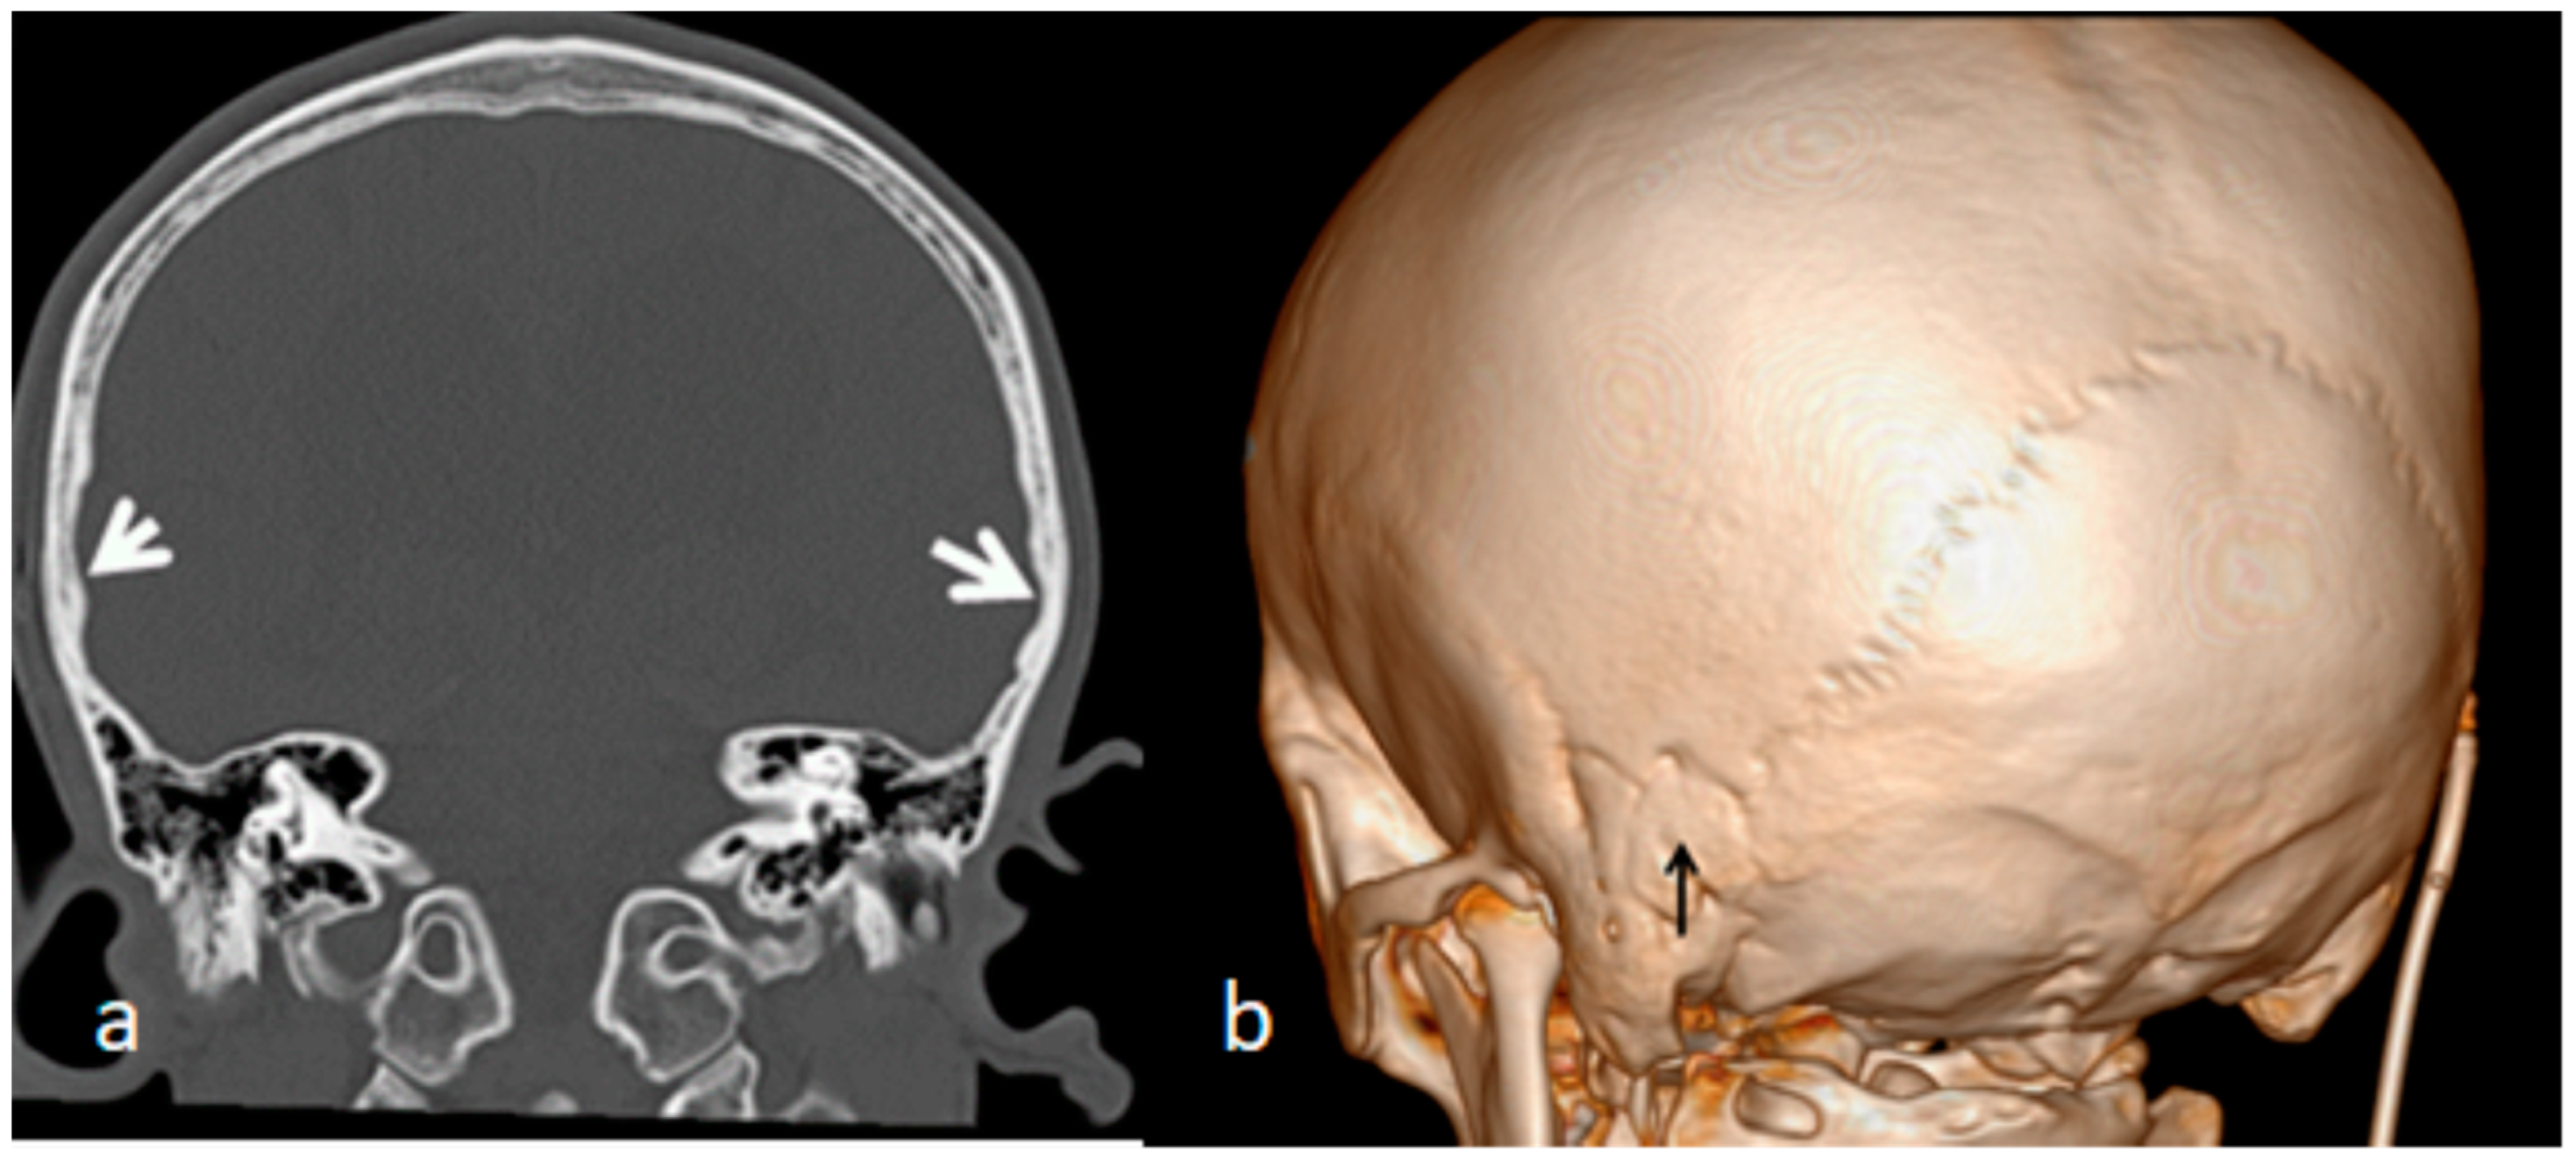

The index case is an 18-year-old Austrian boy who presented with a tall stature (97th percentile), long arms and legs and relative arachnodactyly. An abnormal craniofacial contour resulted in a long, narrow head (prominent forehead and narrow temples), mid-facial hypoplasia and thick, dense eyebrows. A clinical examination of the skull showed apparent and elevated bony ridges, more obvious bilaterally along the squamosal sutures, as well as along the sagittal suture. A family history showed that the 52-year-old father manifested marfanoid habitus (97th percentile). The parents revealed that the child´s subsequent developmental history was near-normal, especially in his first two years. After the age of two years he started to show an awkward gait, and poor balance associated with psychosomatic impairment and signs of increased intracranial pressure. At that age he underwent a series of profound investigations. Serum Chromogranin A (a serum marker of neuroendocrine neoplasia), ammonia, and uric acid, were all within normal values. There were no signs of organic acidopathy, aminoacid excretion pattern, and no increase in MPSs excretion shown through screening for mucopolysacharidosis in urine. Whole exome sequencing did not reveal either Fragile X syndrome nor Dandy–Walker as a syndromic entity. An MRI showed enlarged ventricles caused by a Dandy–Walker-like malformation. The neurosurgeon suggested performing a shunt operation via a surgical perforation of the Blake’s pouch cyst. Unfortunately, the shunt operation altered nothing and the progressive intellectual deterioration became worse. We examined the detailed analysis of the three-dimensional CT scan for both the ecto- and endocranial surfaces of the skull. The scout CT scan of the skull showed a clear scaphocephaly, which signifies the early fusion of the sagittal suture (Figure 4a). The 3D reconstruction CT scan of the skull showed quite clear apparent premature neurocranial suture closure, observed along the squamosal sutures (arrows), and associated with the partial closure of the coronal sutures (there were apparent bony ridges of bilateral squamosal sutures consistent with premature craniosynostosis) (Figure 4b). Coronal computed tomography images of the brain demonstrated a local thumb printing/beaten copper appearance (arrows) of the inner cortex in the region signifying bilateral squamosal fusion (white arrows) (Figure 5a). The early sutural fusion extended posteriorly from the pterion and connected the temporal squama with the inferior border of the parietal bone (bulge-like in the lateral view) (arrow heads). Note the early fusion of the mendosal suture (arrow) (known as the accessory occipital suture) and the implanted shunt (Figure 5b).

Figure 4. (a,b). Scout CT scan of the skull showed a clear scaphocephaly which signifies early fusion of the sagittal suture (Figure 4a). The 3D reconstruction CT scan of the skull shows quite clear apparent premature neurocranial suture closure easily observed along the squamosal sutures (arrows) associated with partial closure of the coronal sutures (there are apparent bony ridges of bilateral squamosal sutures consistent with premature craniosynostosis). The bony ridges along the squamosal suture arching posteriorly from the pterion and connecting the temporal squama with the inferior border of the parietal bone have been all prematurely fused (arrows) (Figure 4b).

Figure 5. (a,b). Coronal computed tomography image of the brain demonstrating a local thumb printing/beaten copper appearance (arrows) of the inner cortex in the region signifying bilateral squamosal fusion (white arrows) (Figure 5a). The early sutural fusion extends posteriorly from the pterion and connects the temporal squama with the inferior border of the parietal bone (bulge-like in the lateral view) (arrow heads). Note the early fusion of the mendosal suture (arrow) (known as the accessory occipital suture) and the implanted shunt (Figure 5b).